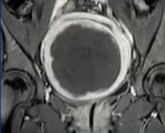

32 yold, G1 P0;3年前发现子宫多发肌瘤。月经量多,贫血(铁补充),痛经。患者此时不希望怀孕,但希望保留未来怀孕的选择。妇科医生建议她子宫切除

![]() |

| 子宫动脉栓塞术前 | 子宫动脉栓塞术前 |

| 术后4个月 | 术后12个月 |